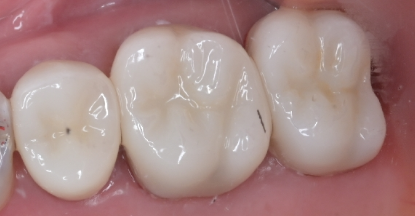

治療後の状態がこちらです。

マイクロエンドを行ったことで、根っこの病巣をしっかり除去できているのがレントゲンを見るとわかります。また、マイクロエンドを選択していただくと保険では扱うことのできない器具や薬剤を使用できるため、より再発のリスクを抑えることができます。今回の患者様は、ホワイトニングもご希望だったので、被せものの色を白く作成しています。そうすることで、他の歯との色味もなじみ患者様も満足されていました。